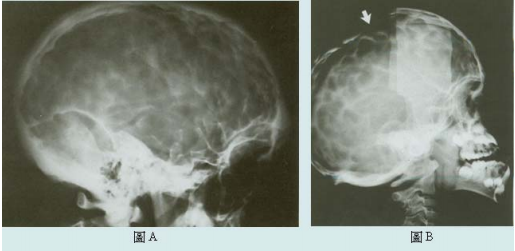

75.圖A及圖B為克魯遜氏症候群(Crouzon syndrome)之頭顱X光影像,其放射線特徵稱為何?

(A)punched-out appearance (B)beaten-metal appearance (C)cotton-wool appearance (D)ground-glass appearance